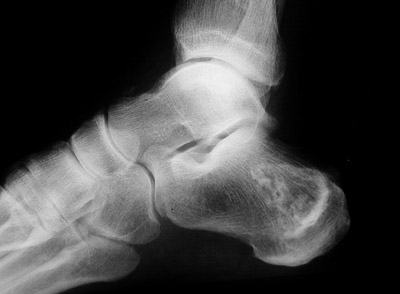

The focal irregular areas of bone remodelling seen above in the calcaneus and below in the distal tibia represent areas of bone infarction. This is an uncommon event, but can occur with sickle cell anemia.